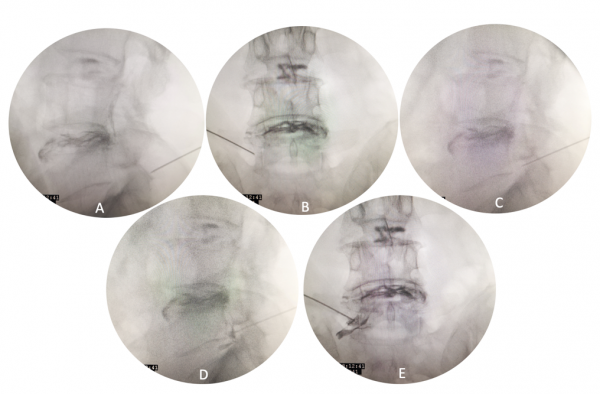

3. 术中透视定位时机:

① 自皮肤穿刺点以40°-45°角穿刺进针至骨性结构时,透视正侧位:使针尖位于关节突关节上;(图3-A,B)

② 针尖斜面面向上关节突外侧,滑过上关节突外侧进入椎间孔,侧位透视:针尖位于椎间孔上三分之一;(图3-C)

③ 针尖在该区域进行探查,引出患者患肢放射痛症状时透视正位,避免针尖超过椎弓根投影内侧缘,从而避免进入椎管导致椎管内麻醉;

④ 注射0.5ml造影剂[2],正侧位观察造影剂弥散形态与出口根走形方向一致。(图3-D,E)

图3